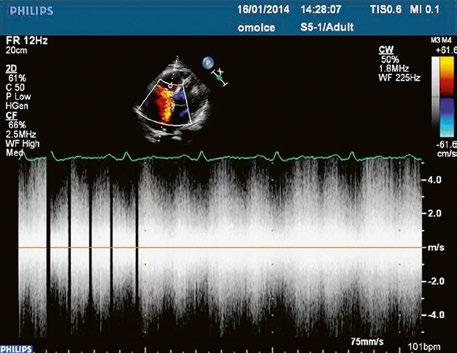

Obr. 45.45 Těžká, dlouhodobě neřešená valvární a subvalvární stenóza plicnice s vysokým gradientem 155/82 mmHg (CW doppler) (viz též Obr. 45.44)

Obr. 45.44 Pacientka s těžkou, dlouhodobě neřešenou valvární a subvalvární stenózou plicnice (také Obr. 45.45 ) s extrémně těžkou hypertrofií přední stěny pravé komory (označena zelenými křížky a šipkou, šíře stěny PK18 mm). Hypertrofie myokardu infundibula přispívá k sekundární subvalvární stenóze plicnice. M mode, parasternální dlouhá osa.

AO – aorta, LK – levá komora, LS – levá síň, PK – pravá komora